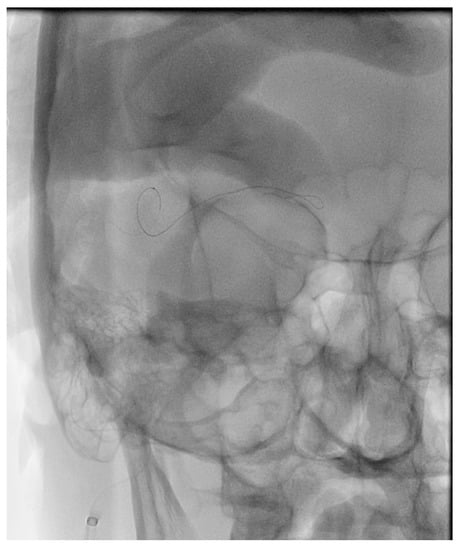

Figure 10. Demonstrates a right sided direct carotid cavernous fistulas (CCF). An occlusion balloon is placed within the right cavernous internal carotid artery (ICA) (white arrow) across the fistula site. Coils are placed within the intercavernous sinus (black solid arrow) through a transvenous inferior petrosal sinus (IPS) approach (white solid arrow). Note the superior petrosal sinus (black arrows), in the lateral projection, with its acute angle off the transverse sinus.

12. Transarterial Via the Cavernous Segment of the ICA (Direct CCF) or Via ICA/ECA Meningeal Branches (Dural CCF)

In the setting of direct CCFs, the tear in the cavernous segment of the ICA provides an endovascular route to the CS. A primary transarterial approach can often be used to embolize these fistulas. Prior to attempting a primary embolization of the fistula, a complete angiogram should be completed, and if adequate cross-filling is identified, a balloon test occlusion (BTO) is recommended. If the patient remains neurologically unchanged, the most effective treatment is often complete ICA occlusion. It is important to remember that the carotid occlusion should extend across the fistula site both proximally and distally to prevent retrograde filling of the fistula from collateral circulation. In the case of failed BTO, the fistula must be treated while maintaining patency of the ICA. In this case, the authors often use a two-catheter system with a microcatheter in the cavernous sinus for embolization and a Scepter balloon catheter (MicroVention, Tustin, CA, USA) to protect the ICA. Using roadmapping technique, a microsystem is then navigated through the tear in the cavernous ICA into the affected CS. An occlusion balloon, or a stent, is placed within the cavernous ICA across the fistula site to protect the ICA during embolization. Coils, Onyx (Covidien, Irvine, CA, USA), or a combination of both are then used to obliterate the fistula. Alternatively, in some cases of direct CCF, a combined transarterial and transvenous approach is the safest and most effective way to embolize the fistula. Figure 10 demonstrates a right sided direct CCF with venous drainage through the intercavernous sinus into a dilated left CS. In this case, the authors first navigated a Hyperform balloon (Covidien, Irvine, CA, USA) across the tear in the right ICA. Next, a microsystem was navigated through the left IPS, into the left CS, and subsequently into the intercavernous sinus. With the balloon inflated to prevent coil migration into the right ICA, the intercavernous sinus was embolized with coils, effectively obliterating the fistula. Final angiograms showed no evidence of residual fistula, and the patient had complete resolution of her preoperative symptoms.